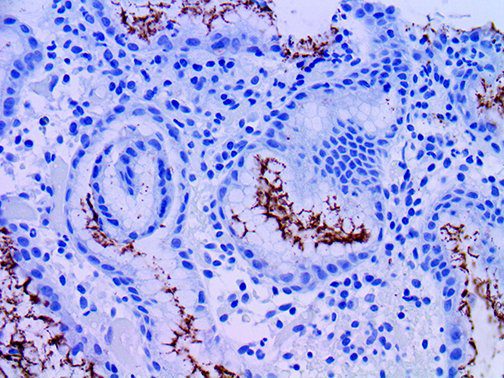

It is the ICU physician who is most likely to witness one of the deadliest manifestations of the abnormal immunological response, the cytokine storm syndrome (CSS). This response is also referred to by some as the cytokine release syndrome (CRS). CSS is characterized by continuous activation and expansion of macrophage and lymphocyte populations, which secrete large amounts of cytokines, causing the cytokine storm. This massive cytokine release is akin to hemophagocytic lymphohistiocytosis (HLH) disease, a syndrome characterized by initial unchecked and persistent activation of cytotoxic T lymphocytes and NK cells.

Clinical and laboratory manifestations of HLH include fever, enlarged liver and/or spleen, neurologic dysfunction, coagulopathy, liver dysfunction, cytopenias (i.e., low levels of erythrocytes, leukocytes, and/or platelets), hypertriglyceridemia, hyperferritinemia, hemophagocytosis, and eventually diminished NK cell activity as the immune system becomes progressively paralyzed. HLH can be familial (primary HLH) or secondary to another disease process (sHLH), such as rheumatic disease, in which it is referred to as macrophage activation syndrome (MAS, characterized by elevated ferritin).